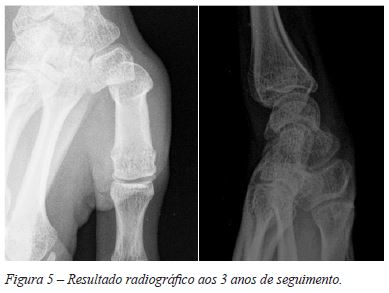

Não se verificaram complicações agudas ou tardias e a doente evidenciou excelente evolução clínica e funcional com pontuação máxima no score de Kapandji (Figura 4) um mês após cirúrgia e regresso sem restrições à prática de violoncelo aos 3 meses após cirurgia. O controlo radiográfico demonstrou redução da subluxação articular (Figura 5), que se mantém aos 3 anos de seguimento.